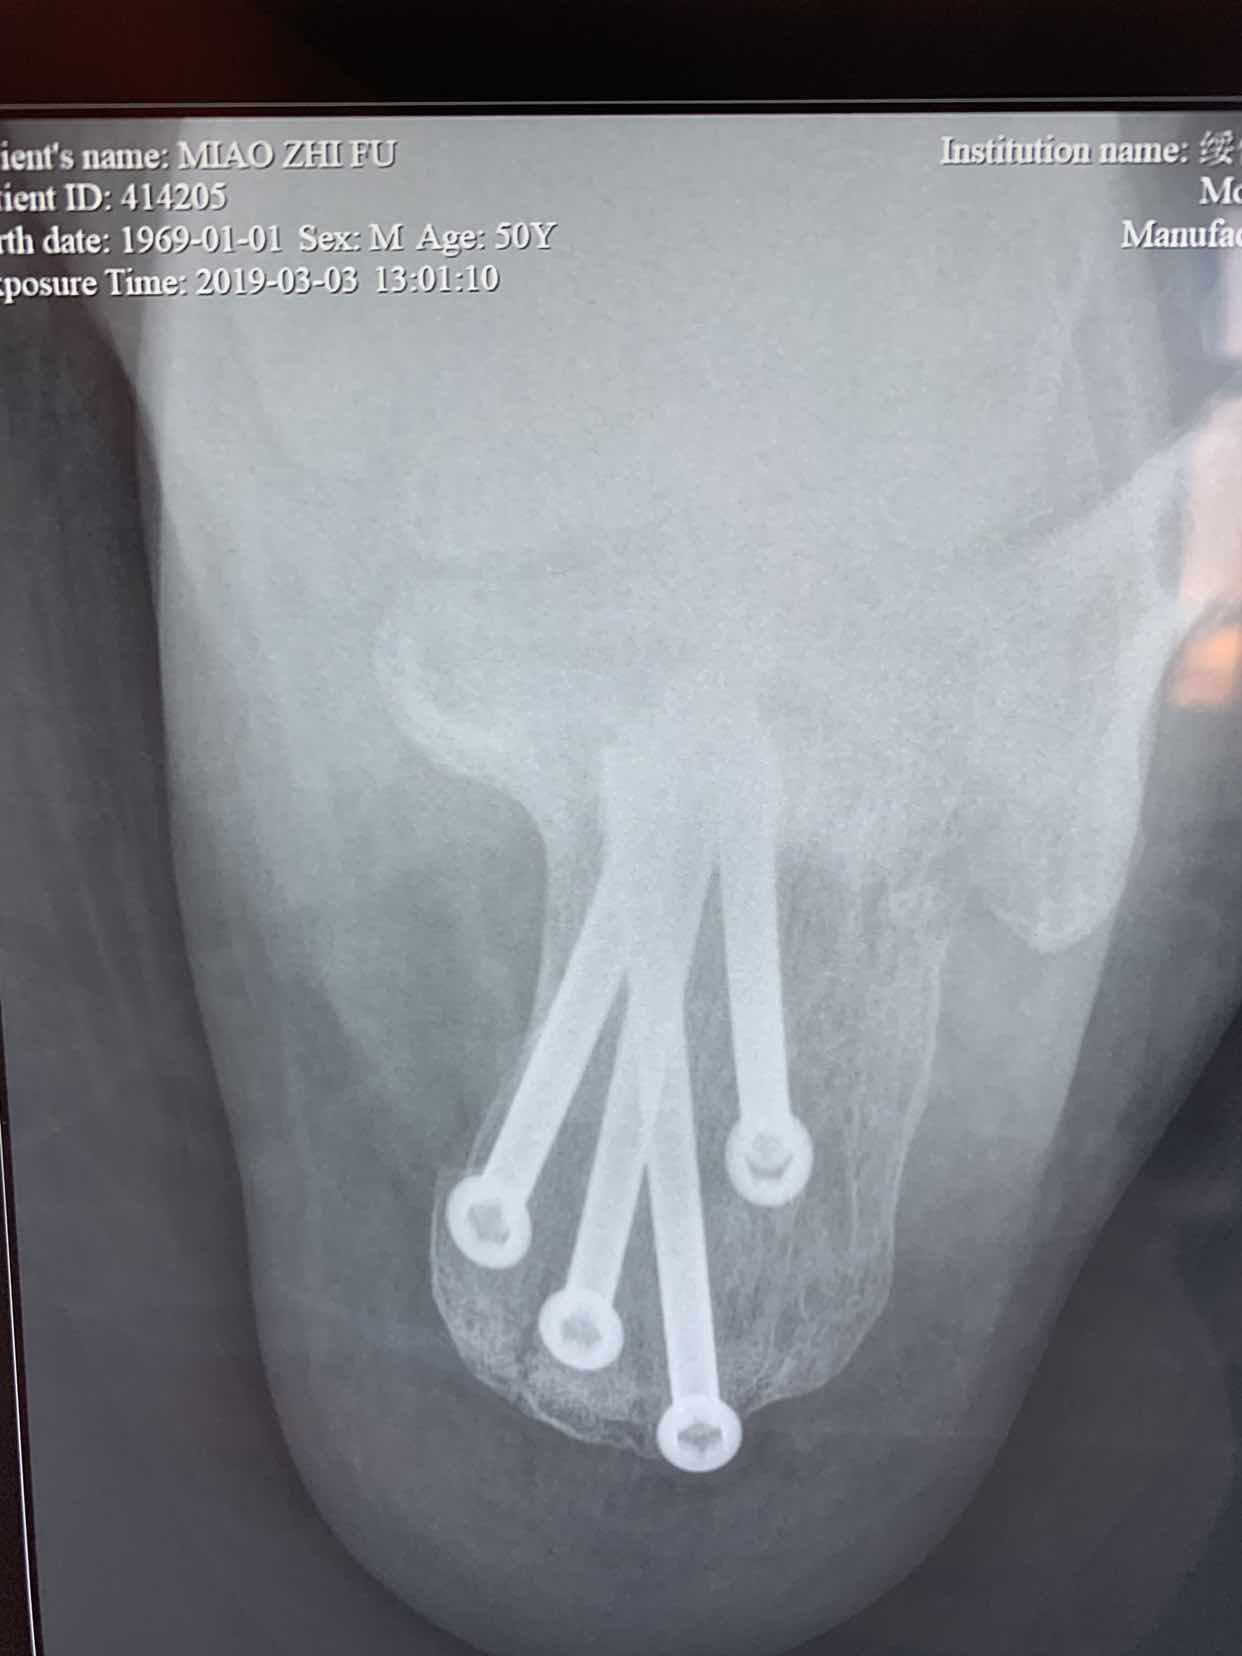

诊断为左侧跟骨粉碎性骨折。在腰麻下行闭合复位空心钉内固定术。术后恢复较好。